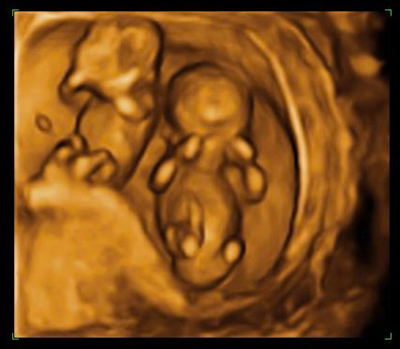

An image showing an early diagnosis of twins.

This illustration shows normal monochorionic twins, in which a single placenta is shared by two fetuses and no complications are present. The umbilical cord of each twin inserts anywhere into the placenta. Each twin has its own amniotic sac with a normal amount of amniotic fluid.